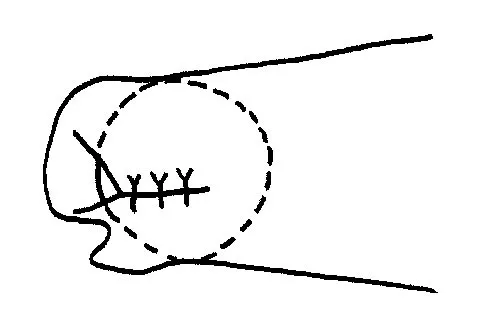

When compared to traditional open repair through a posterior incision, percutaneous Achilles tendon repair clearly results in a reduction of what complication?

Explanation